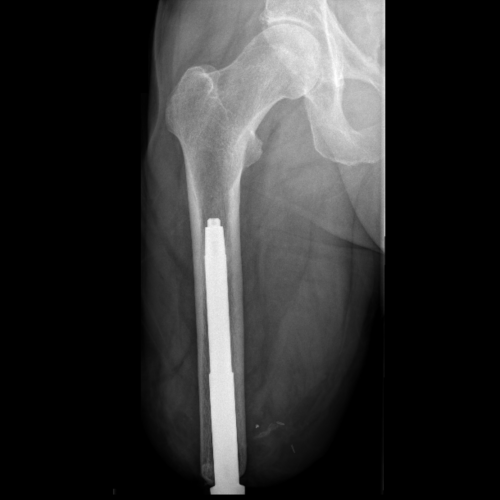

image of osseointegration

image of before osseointegration

Before Osseointegration

Osseointegration is a procedure in which a titanium implant is surgically inserted into the bone to provide a stable anchor for prosthetic limbs. The implant fuses with the bone over time, bypassing the need for traditional socket-based fittings.